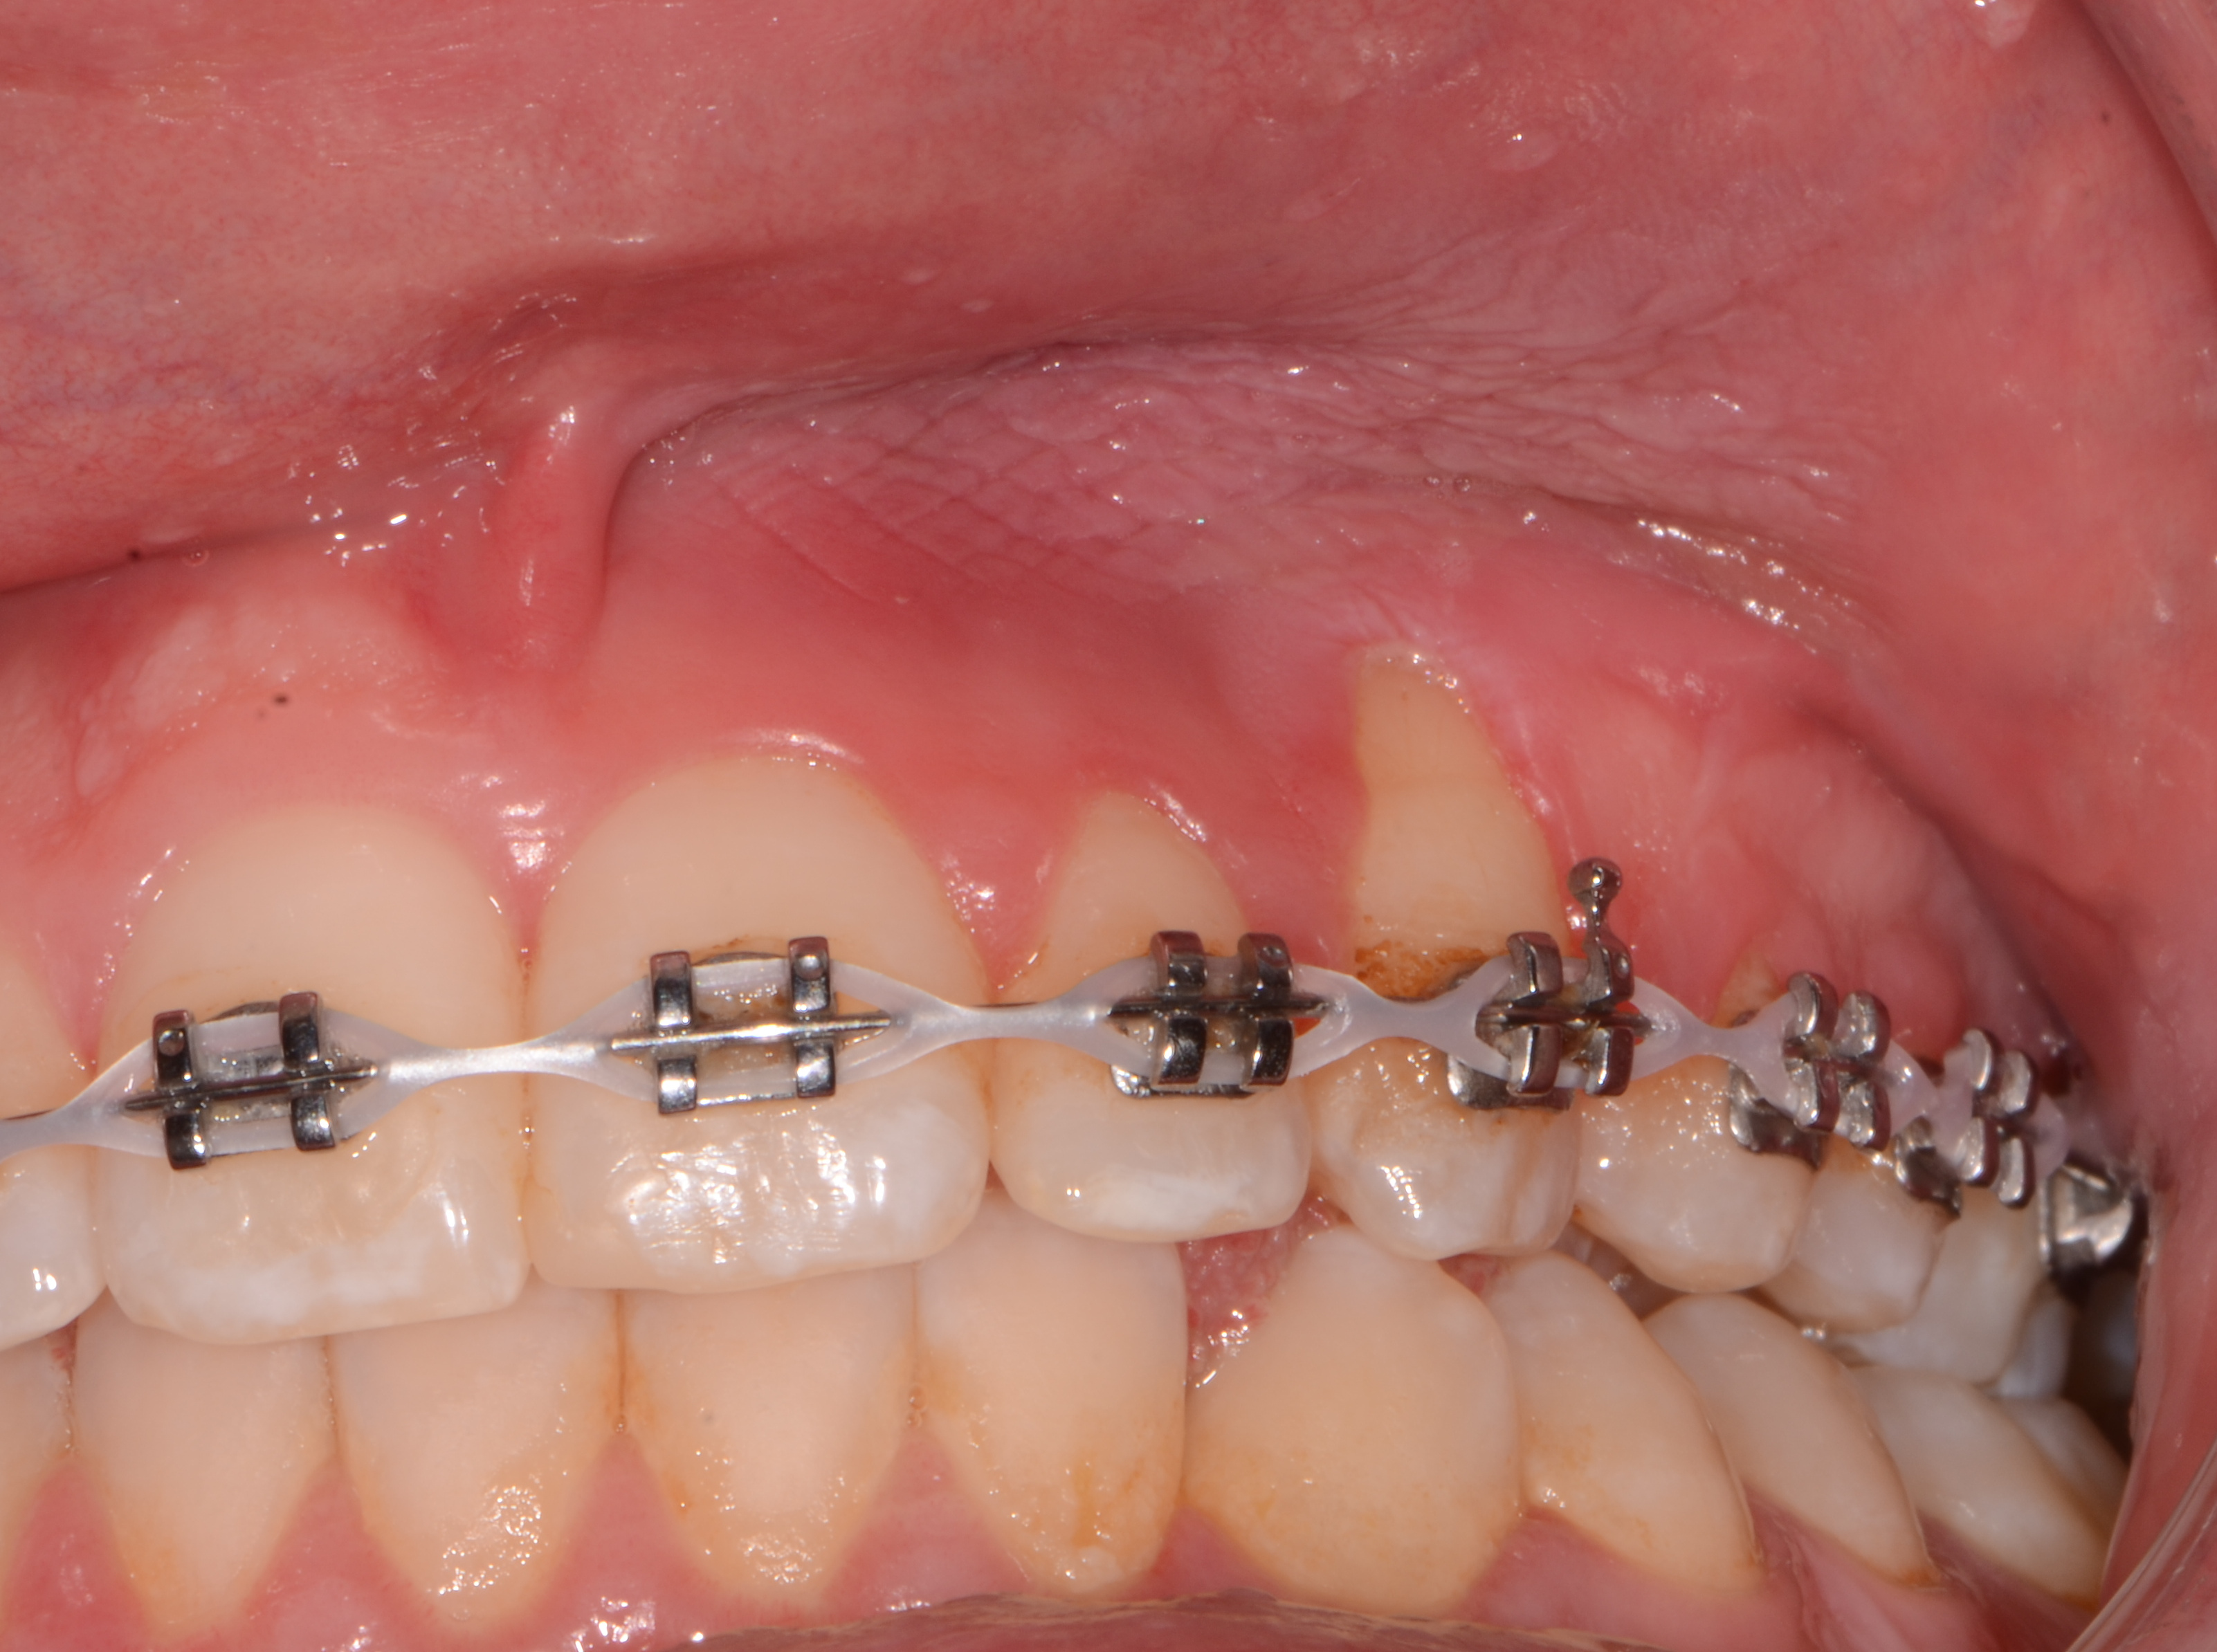

Grav initialkaries